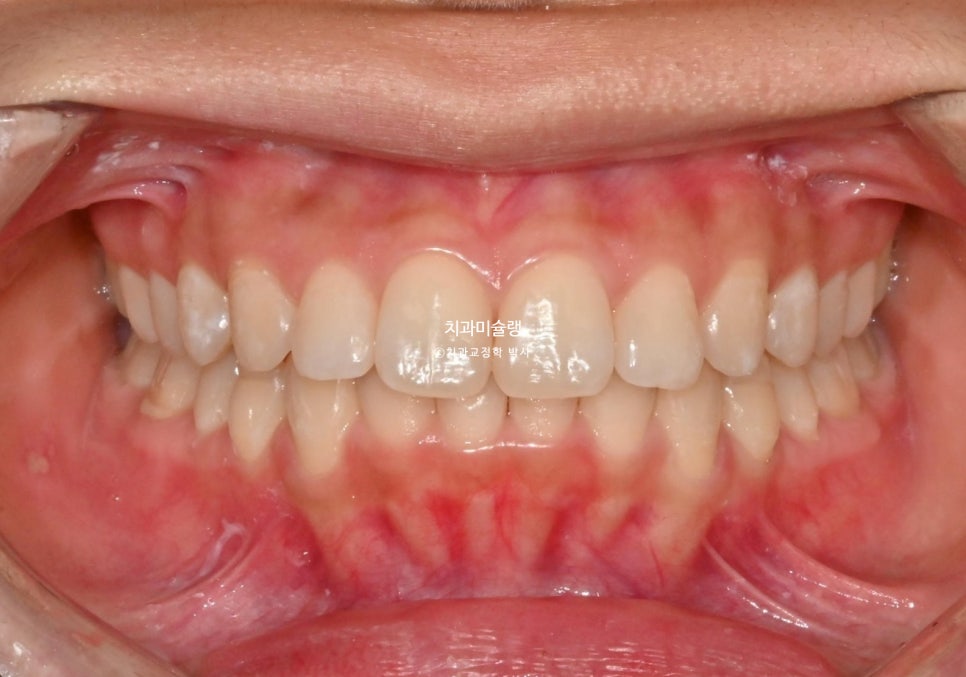

중심선 불일치와 과개교합이 보입니다.

중심선은 정확히 맞으며 과개교합은 개선되었습니다. 브라켓 주변부 양치가 안되어 안타깝게도 충치가 좀 생겼습니다. 어금니 교합관계는 1급관계를 달성.

| 중심선 | 불일치 | 일치 |

| 과개교합 | 있음 | 개선됨 |

| 어금니 교합 | 2급 관계 | 1급 관계 |

| 입술부전증 | 있음 | 개선됨 |